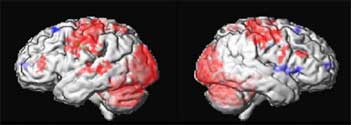

Decreased metabolism in AD compared to controls

One year of DBS compared to baseline

Positron emission tomography scans of 6 patients with Alzheimers disease

showing areas of decreased glucose utilization before surgery in

blue which are reversed with DBS after 1 month or 12 months of DBS.

Restoring glucose utilization suggests that these brain areas that were shut

down are once again active.